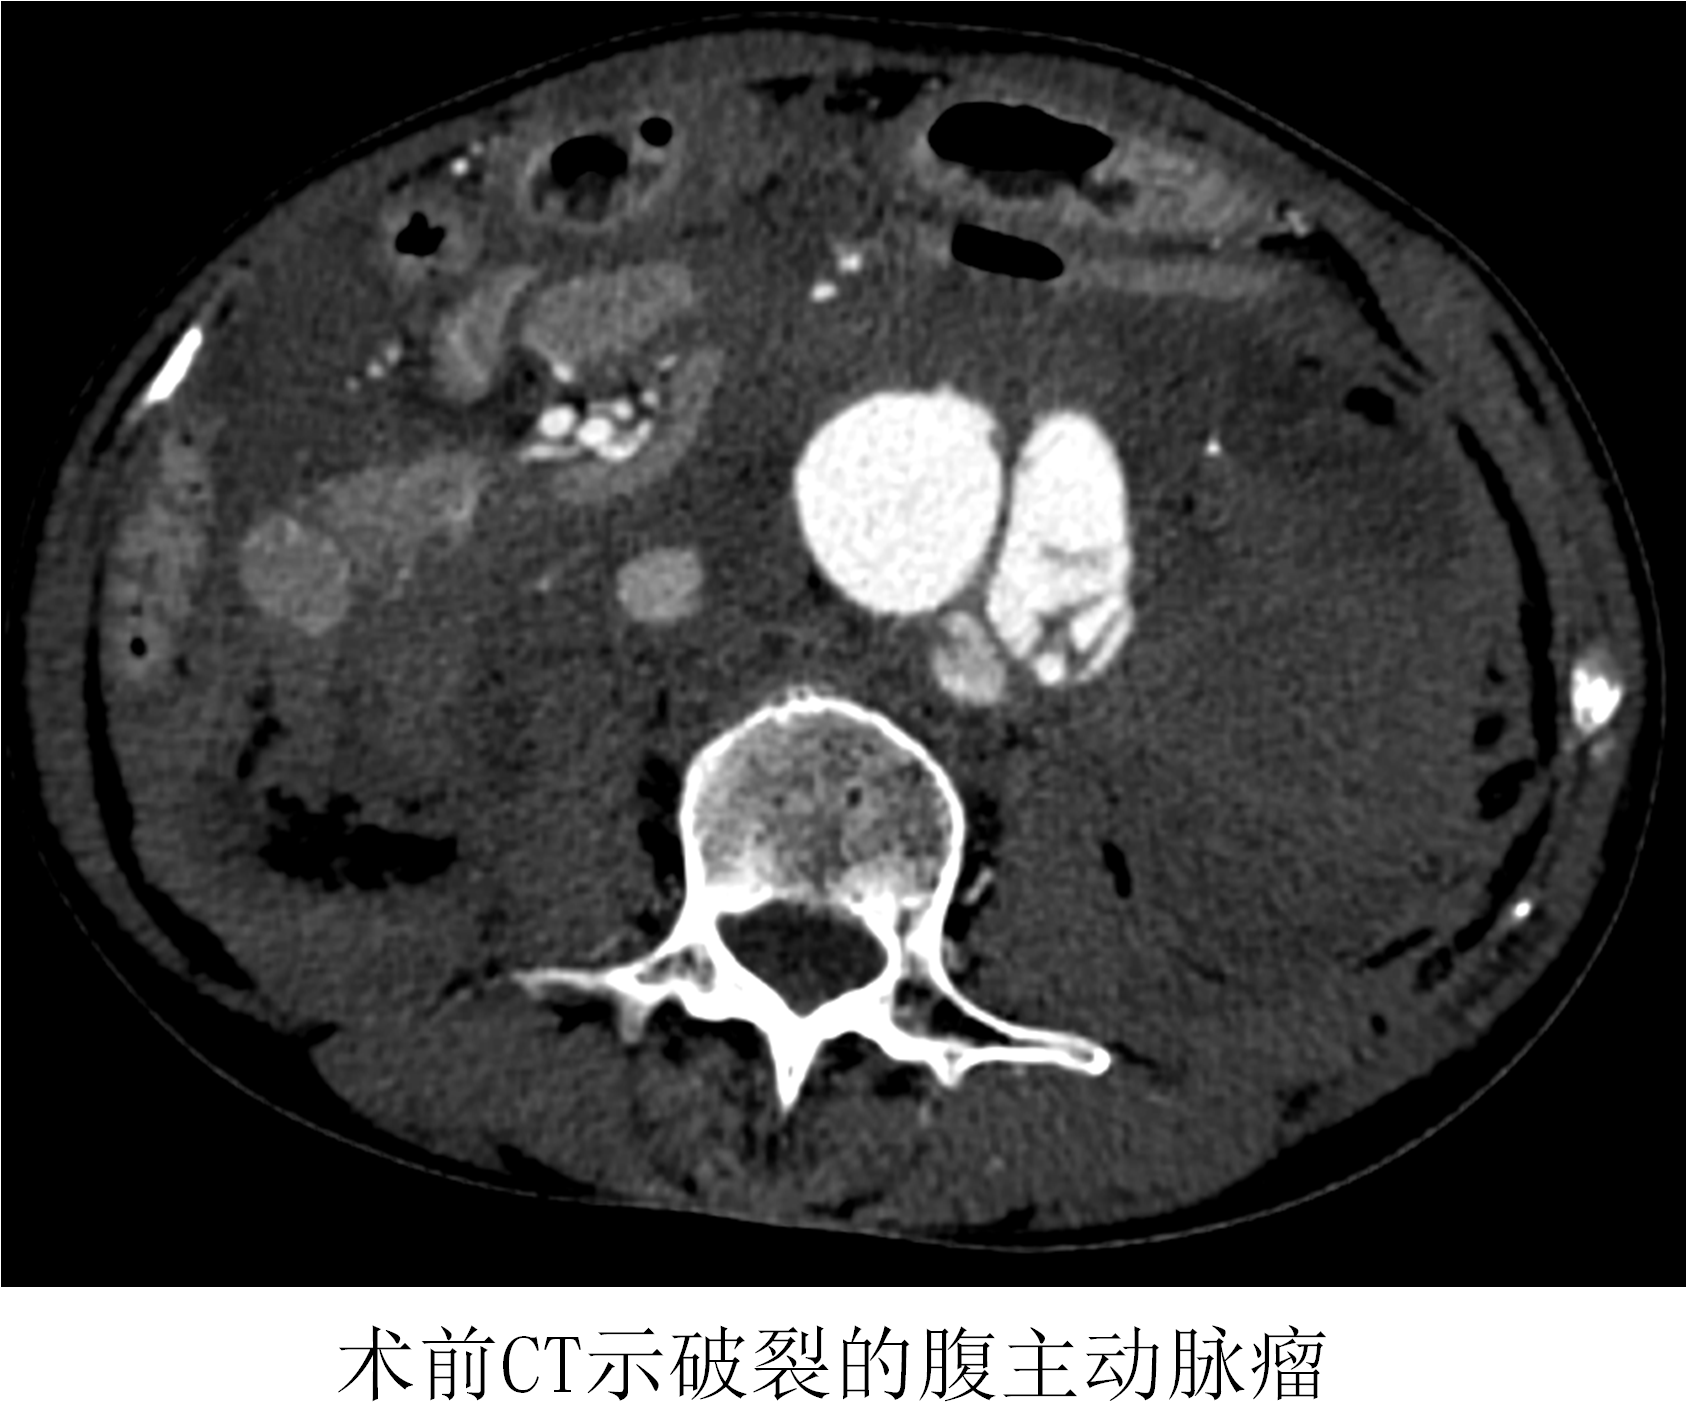

時(shí)間就是生命!在來不及全麻的情況下,薛冠華當(dāng)機(jī)立斷,局麻手術(shù)。手術(shù)由薛冠華主刀、倪其泓和王預(yù)立醫(yī)師共同協(xié)助,在麻醉醫(yī)師黃丹、手術(shù)室護(hù)士夏悅和放射科技師馬鋆的配合下緊張進(jìn)行。薛冠華通過精準(zhǔn)定位,在避免影響內(nèi)臟血管的同時(shí),采用腔內(nèi)技術(shù)在短短30分鐘內(nèi)就將腹主動(dòng)脈瘤的破口通過覆膜支架封堵,有效阻止了進(jìn)一步出血。患者的血壓開始回升,情況逐漸平穩(wěn),手術(shù)順利完成;颊咿D(zhuǎn)入重癥監(jiān)護(hù)室后意識(shí)慢慢恢復(fù),術(shù)后10天復(fù)查CT顯示破裂的腹主動(dòng)脈瘤隔絕良好,已于近期康復(fù)出院。